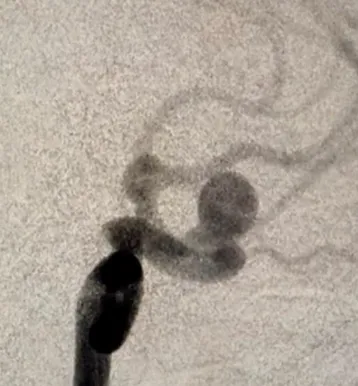

Аневризмы мозговых артерий – это патология сосудов, при которой происходит выпячивание стенки артерии. По форме выпячивания различают мешотчатые и веретенообразные (фузиформные) аневризмы. Причина появления аневризма доподлинно неизвестна. Среди этиологических факторов могут выступать врожденные предрасположенности (дефекты мышечного слоя стенки мозговых сосудов); атеросклеротические (сочетаются с врожденными дефектами стенки мозговых сосудов); Эмболические, инфекционные, травматические факторы

МРТ головного мозга, церебральная ангиография, КТ-ангиография.

При выявлении неосложненных аневризм проводится плановое нейрохирургическое вмешательство методами клипирования аневризмы или баллонной ангиопластики (эндоваскулярное закрытие выпячивания стенки сосуда).